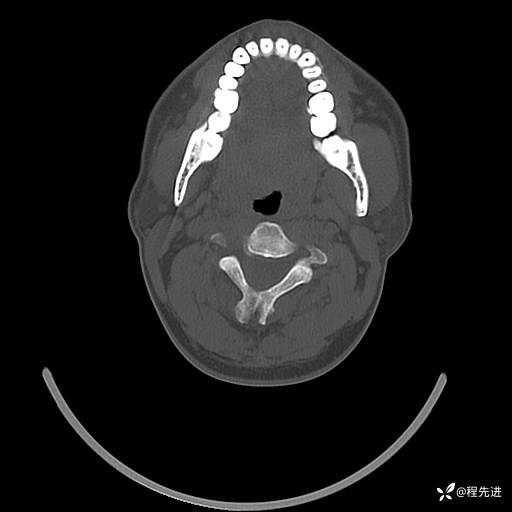

CT平扫+增强: